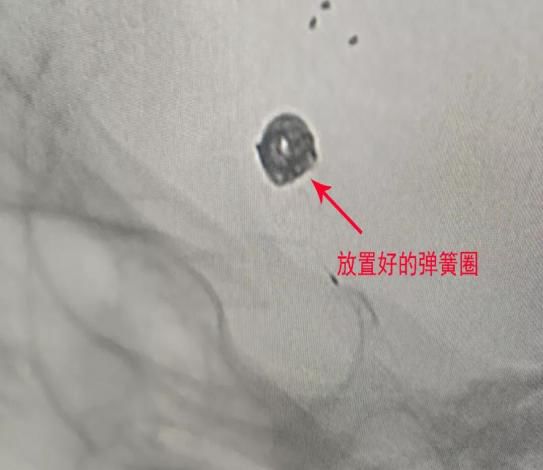

(6)2018年12月13日开展第一例颅内动脉瘤栓塞术。

患者:赵某  女性 48岁 河南省光山县

图片